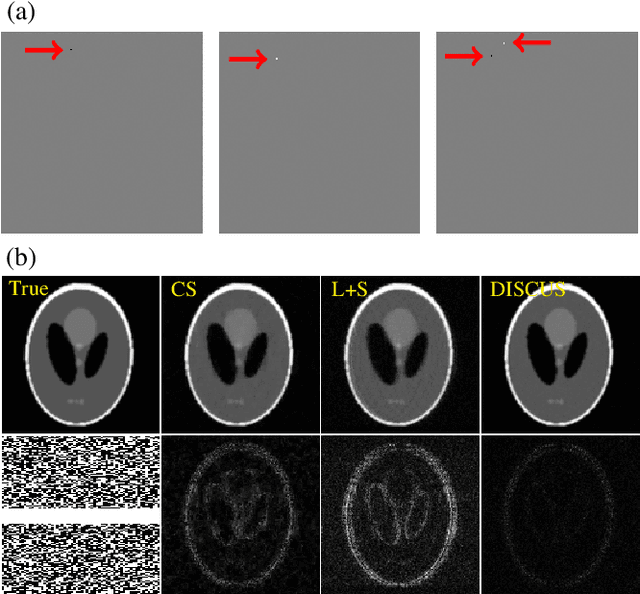

Abstract:High-quality training data are not always available in dynamic MRI. To address this, we propose a self-supervised deep learning method called deep image prior with structured sparsity (DISCUS) for reconstructing dynamic images. DISCUS is inspired by deep image prior (DIP) and recovers a series of images through joint optimization of network parameters and input code vectors. However, DISCUS additionally encourages group sparsity on frame-specific code vectors to discover the low-dimensional manifold that describes temporal variations across frames. Compared to prior work on manifold learning, DISCUS does not require specifying the manifold dimensionality. We validate DISCUS using three numerical studies. In the first study, we simulate a dynamic Shepp-Logan phantom with frames undergoing random rotations, translations, or both, and demonstrate that DISCUS can discover the dimensionality of the underlying manifold. In the second study, we use data from a realistic late gadolinium enhancement (LGE) phantom to compare DISCUS with compressed sensing (CS) and DIP and to demonstrate the positive impact of group sparsity. In the third study, we use retrospectively undersampled single-shot LGE data from five patients to compare DISCUS with CS reconstructions. The results from these studies demonstrate that DISCUS outperforms CS and DIP and that enforcing group sparsity on the code vectors helps discover true manifold dimensionality and provides additional performance gain.